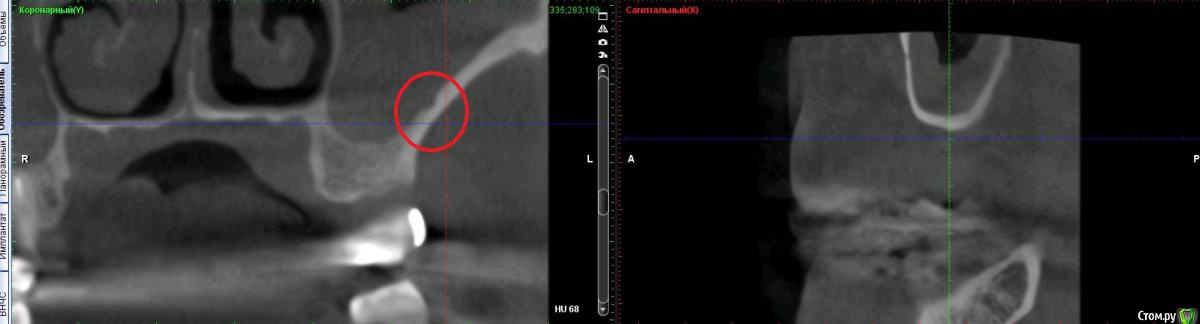

Дмитрий Л. Опубликовано 16 ноября, 2018 Поделиться Опубликовано 16 ноября, 2018 (изменено) Здравствуйте всем)Ситуация такая: старый мост 24-28. 28 симптоматичен, пациент принимает аб и противовосп. Имеется: - 24 перирадикулярные изменения (асимптомно)- 28 перирадикулярные изменения (обострение)- утолщение слизистой гайморовой (асимптомно)- невозможность имплантации в обл 26 (высота кости не позволяет) Пожелания пациента:- удаление 28 - желание сохранить мост - имплантация - нежелание носить съемную конструкцию Как планирую я:- перелечить 24, кальций 2-6 мес.- удалить 28- изготовить съёмник- выждать 4-6 мес. Повторить КТ, оценить гайморовую- имплантация 25, имплантация "где-то в обл 27" - всеми силами избежать синуса Мои грёзы:1. Ставить вблизи 24 - риск. Нужно лечить 24... реэндо... долго... может удалить? 2. Я верю, что причина хр гайморита - 28. Так ли это? Стоит ли ожидать позитивной динамики? 3. На сколько уйдёт кость после удаления 28 за 4-6 мес.? Её и так мало... Станет ли меньше? Графтить 28 не хочу. Там микробы. 4. Объём кости в обл 27-28 требует коротышку. Первыми приходят на ум Штрауман 6 мм (4 мм в кости, станет красиво) или ЭниРидж (бикортакально, скорее всего в пазуху на 1-2 мм). Нюанс в том, что я не работал этими системами... И коротышки не ставил. В общем придётся искать наборы, но это мои проблемы. 5. Итоговая конструкция: мост 25-27. При чём 27 имеет длину 4-6 мм, не слишком ли короткая дистальная опора? Вот спланировал приблизительно так... Надеюсь на отклик. Изменено 16 ноября, 2018 пользователем Дмитрий Л. Ссылка на комментарий

Дмитрий Л. Опубликовано 16 ноября, 2018 Автор Поделиться Опубликовано 16 ноября, 2018 (изменено) Bier, вы в целом согласны с планом идти отстрочено?Отметили, на сколько утолщена слизистая? Стучали бы по такой?) Irouil, предлагаете- перелечить 24, кальций 2-6 мес.- удалить 28- изготовить съёмник- выждать 4-6 мес. Повторить КТ, оценить гайморовую ?Или вы бы планировали синус в обл 26 тоже? Спасибо за комментарии. p.s. Это ведь сосуд? Изменено 16 ноября, 2018 пользователем Дмитрий Л. Ссылка на комментарий